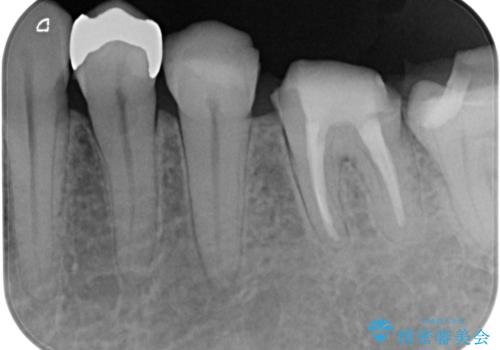

- 近医にてむし歯治療として根管治療を受けるも、痛みが全く改善しないとのことで来院された患者様です。

痛みが継続するため、「根管治療」と検索したところ、「ラバーダム」の重要性を知るところとなったようです。

根管治療を実施した後に、フルジルコニアクラウンにて補綴することとしました。

奥歯に痛みがあるとのことで診察を行ったところ、海外(アメリカ)にて処置をした手前の歯が既に失活していることが分かりました。なお、治療を行った大臼歯はレントゲン写真上の治癒が認められました。